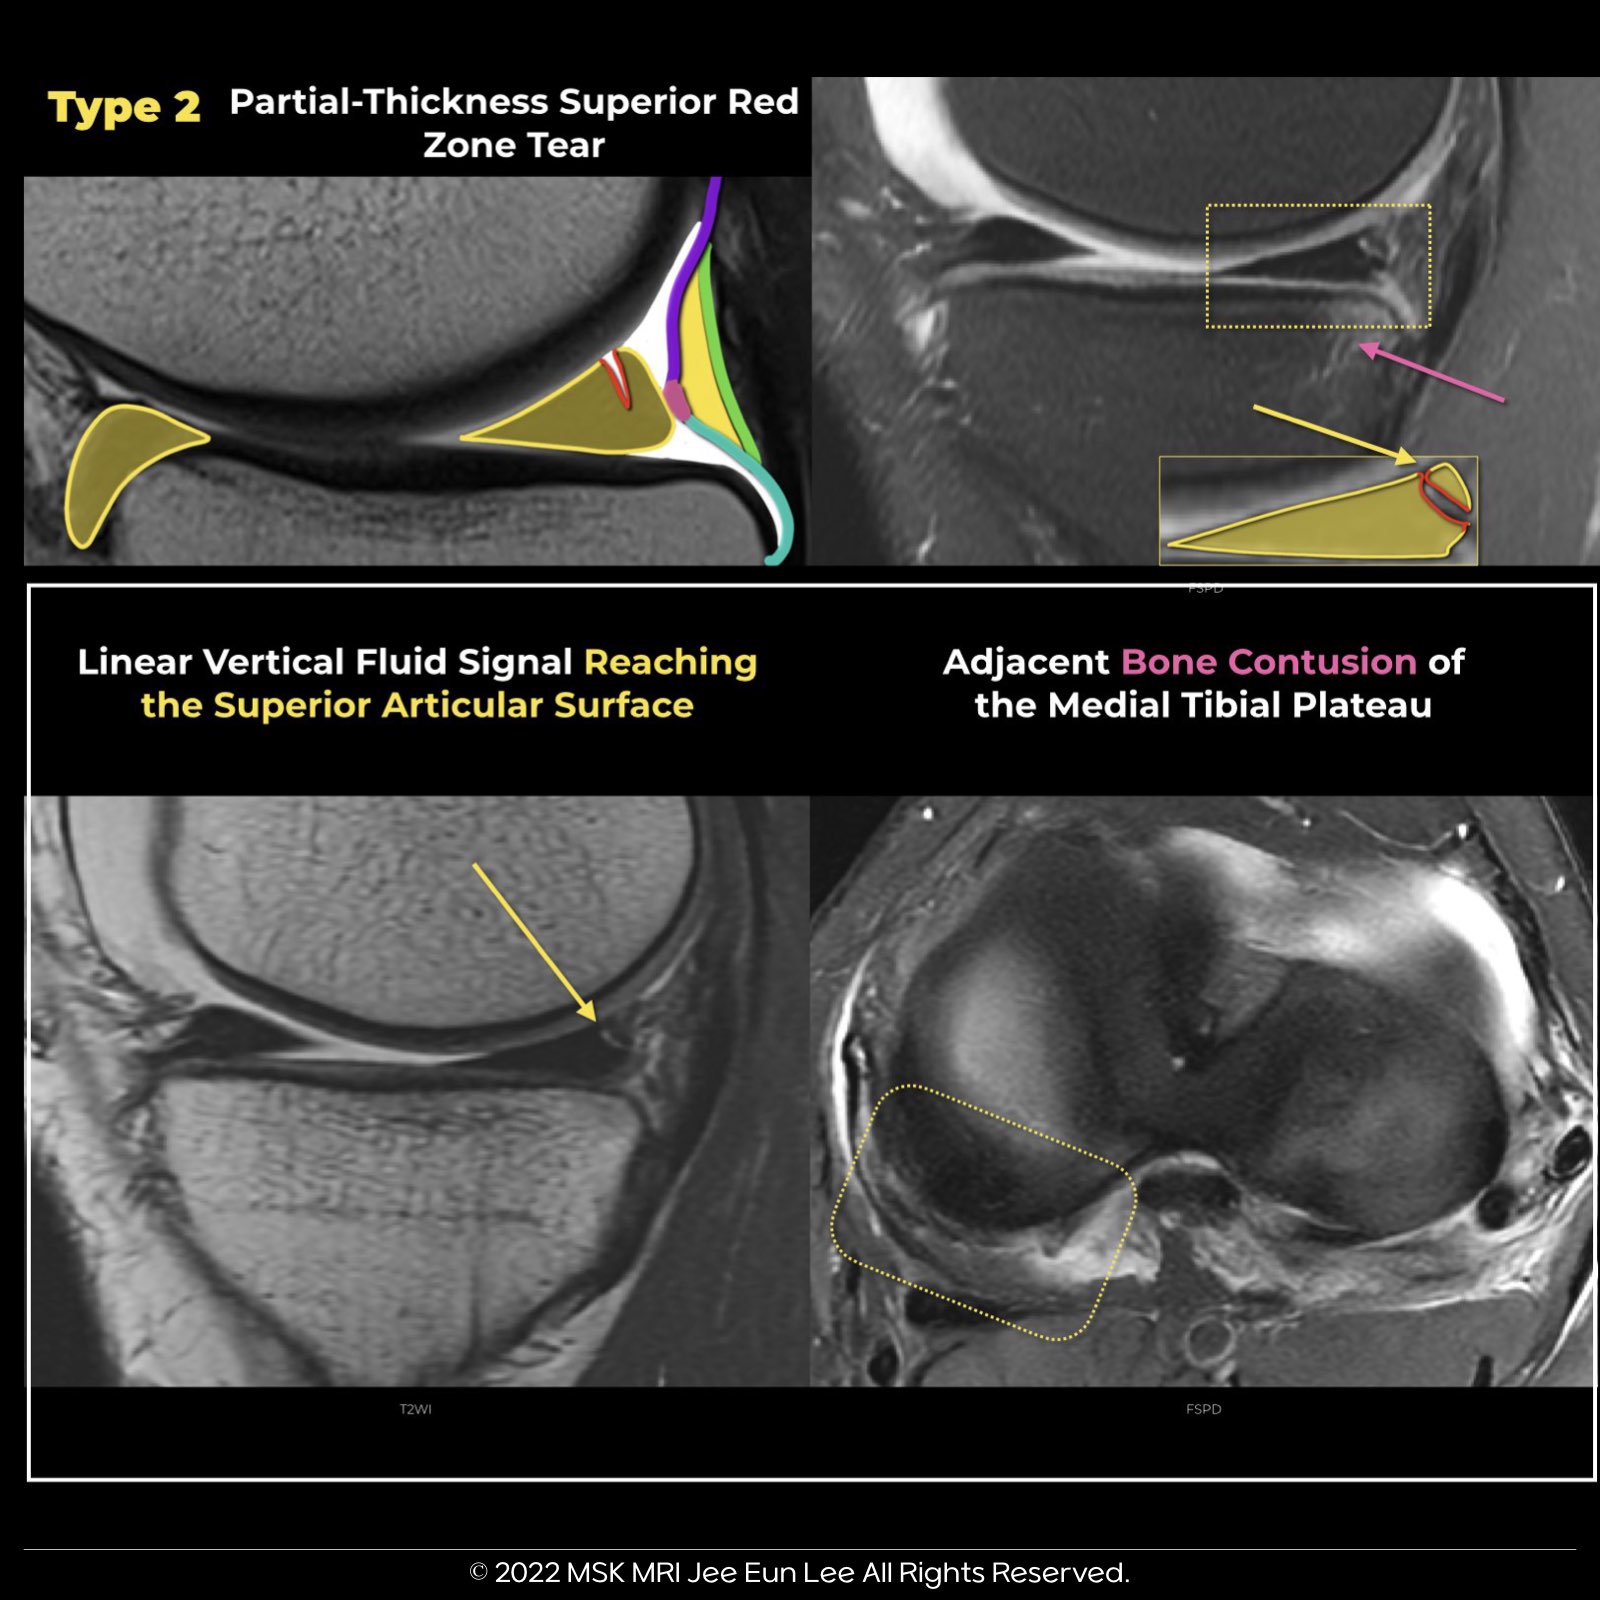

Type 2 Ramp Lesion: Partial Superior Lesion

- Type 2 Ramp Lesions are characterized by peripheral partial-thickness tears involving the superior margin of the posterior horn of the medial meniscus.

- These tears retain intact meniscocapsular attachments to the posterior horn.

- This type of tear pattern is generally considered more stable compared to full-thickness meniscocapsular tears.

MRI Findings:

- The image depicts a Type 2 Ramp Lesion, showing a partial thickness superior vertical tear extending through the posterior horn of the medial meniscus, with a linear vertical fluid signal reaching the superior articular surface.

- Additionally, a peripheral partial tear of the posterior horn of the medial meniscus affects the femoral articular surface, accompanied by a meniscocapsular ligament tear.

- Bone Marrow Edema:

This is present in the anterior aspect of the medial femoral condyle and posterior margin of the medial tibial plateau, indicative of recent contrecoup injury.